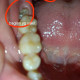

ALo dok, izin diskusi pasien wanita usia 33 tahun datang dengan keluhan nyeri gigi geraham kanan menjalar hingga telinga, demam disangkal, masih bisa membuka mulut >2 jari, namun saat foto tenggorokan pasien baru menyadari ada bintik putih di bagian tenggorokan, nyeri tenggorokan disangkal, sudah di coba gargle tp bintik putih tidak hilang, kira2 ini kondisi apa ya dok? apakah tonsilloliths? dan apakah cukup kita fokus ke nyeri giginya terlebih dahulu mengingat tidak ada keluhan di tenggorokan? mohon diskusinya dok terima kasih